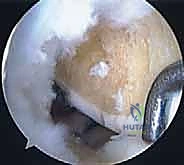

الخطوة الرابعة: إدخال الطعم وتثبيته

من خلال شق جراحي صغير (Mini-arthrotomy)، يتم سحب الطعم بلطف إلى داخل الركبة باستخدام الخيوط التي تم تمريرها عبر الأنفاق العظمية. يتم التأكد من استقرار السدادات العظمية داخل الأنفاق.

الخطوة الخامسة: الخياطة المحيطية الدقيقة (Peripheral Suturing)

هذه هي الخطوة الأكثر حيوية. يجب خياطة محيط الغضروف الهلالي الجديد بكبسولة الركبة للمريض بشكل محكم ومتقارب جداً. يستخدم الدكتور هطيف تقنيات خياطة متعددة بالمنظار: